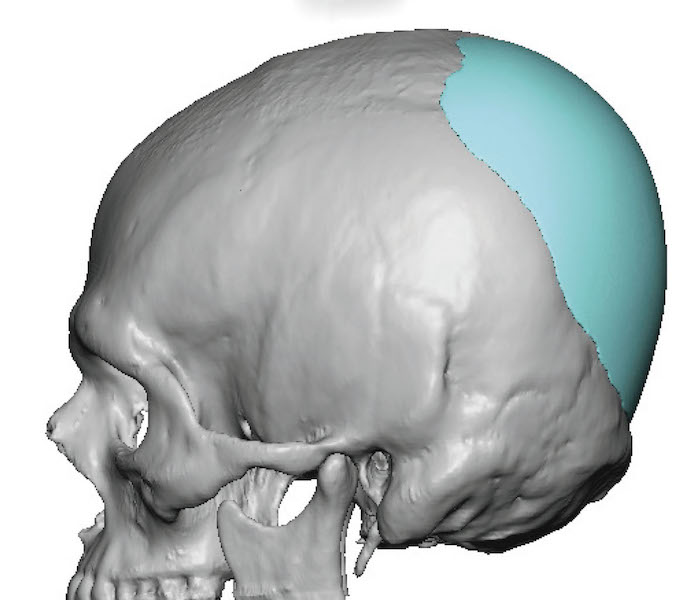

Patient 4

Desire for an improved head shape so that it looks rounder and not so peaked or sloped.

Placement of custom skull implant for parasagittal augmentation to create a rounder head shape. An example of what appears to be a high sagittal crest that is really low parasagittal skull areas.

Desire for an improved head shape so that it looks rounder and not so peaked or sloped.

Placement of custom skull implant for parasagittal augmentation to create a rounder head shape. An example of what appears to be a high sagittal crest that is really low parasagittal skull areas.